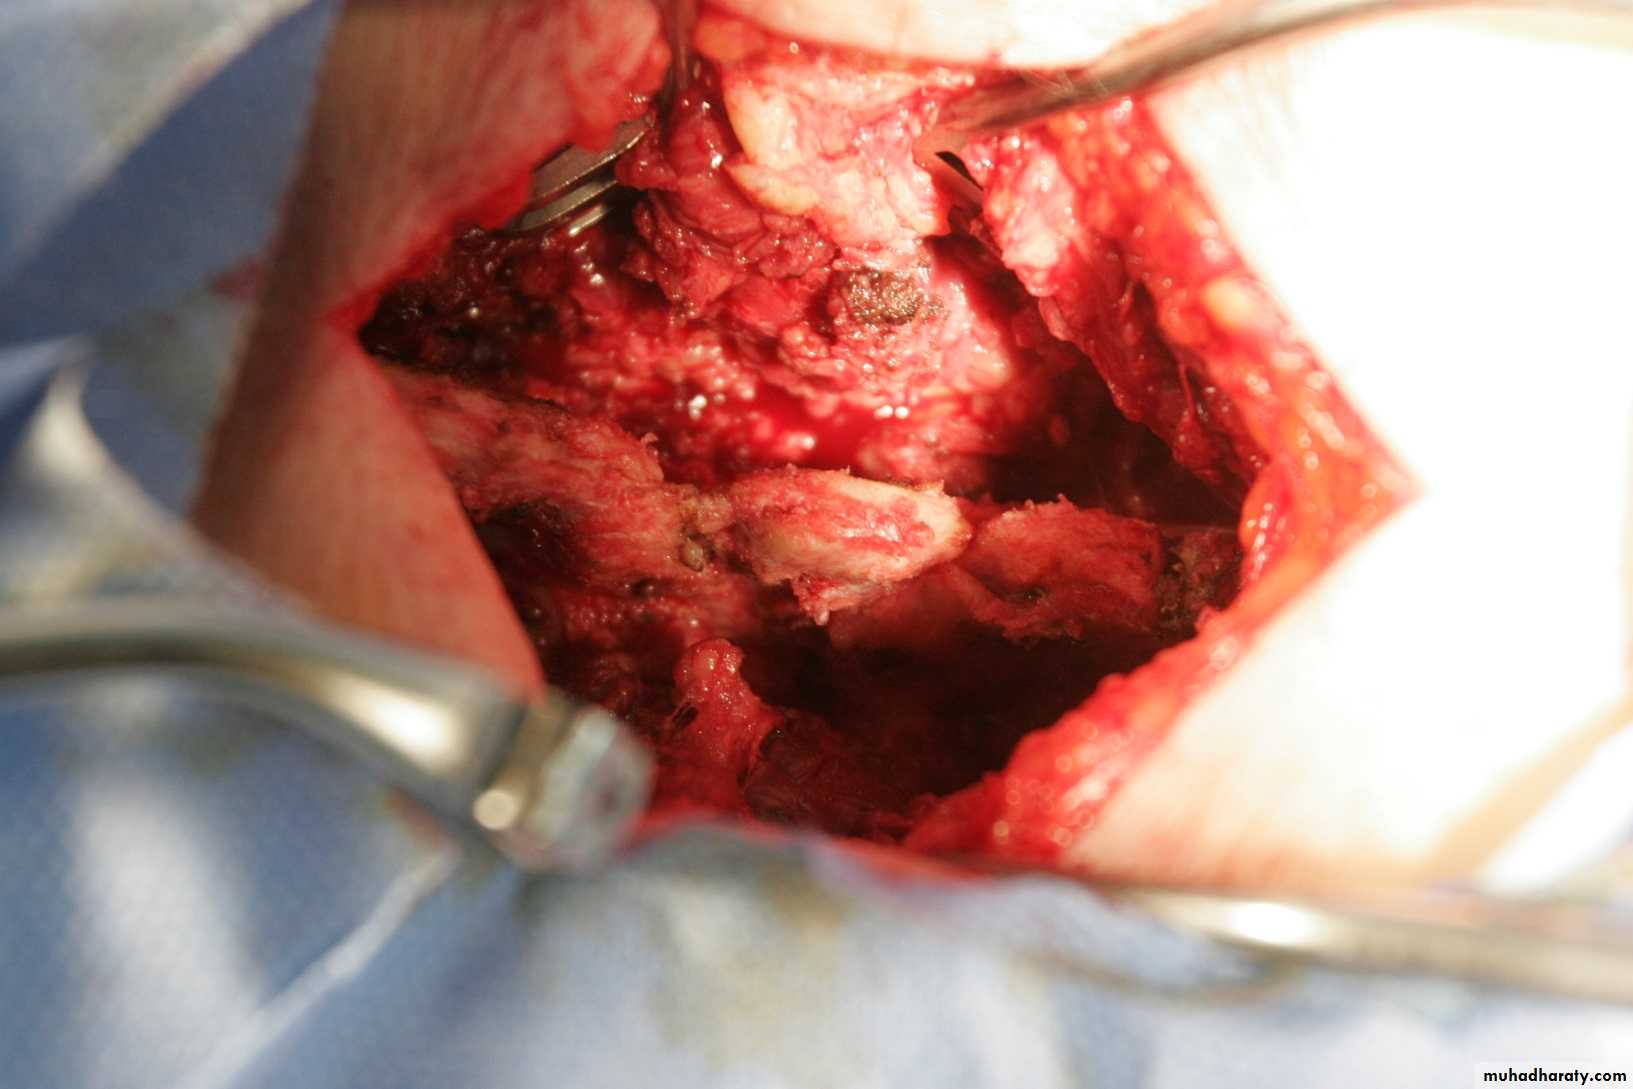

Decompression Laminectomy

Non instrumented spinal fusionInstrumented spinal fusion

Spinal fusion with fixation

A combination of previous surgeries

Surgical Procedures